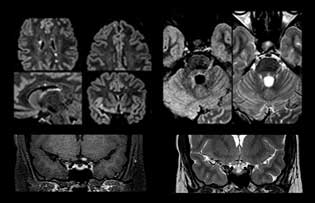

Imaging MS in brain

For MS imaging in the brain, Dr. Savatovsky uses 3D FLAIR as the basic sequence to visualize the lesions and assess the situation and lesion load. “We count the lesions in each location to determine if the criteria of the disease are fulfilled. We use a T2-weighted sequence because our neurologists are used to it. We compare the lesion load on FLAIR with a 3D T1 post-contrast sequence to help us determine whether lesions are old or new. We typically administer the contrast before the patient enters the machine because it shortens the examination time and allows to visualize active lesions that tend to be more visible after several minutes. When a differential diagnosis is difficult, we add sequences such as susceptibility imaging, because some focal MS lesions have a small vein in the center[3].”

MS imaging in spine is more complicated

“For MS imaging in the spine, the basic examination includes a sagittal T2 and a post-contrast sagittal T1-weighted sequence in the whole spine. These are done in two stacks and using thin slices, for example 2 mm, without gap. As in the brain, the T2-weighted sequence visualizes the overall lesion load and helps determine if lesions are old or new. The post-contrast T1- weighted sequence helps in assessing if a lesion is new. We will sometimes add a T1 inversion recovery sequence, which has very good sensitivity, if we don’t find any lesions on T2,” Dr. Savatovsky says. “Additionally, if there is contrast enhancement outside the spine, it’s usually not MS but another kind of inflammation.”